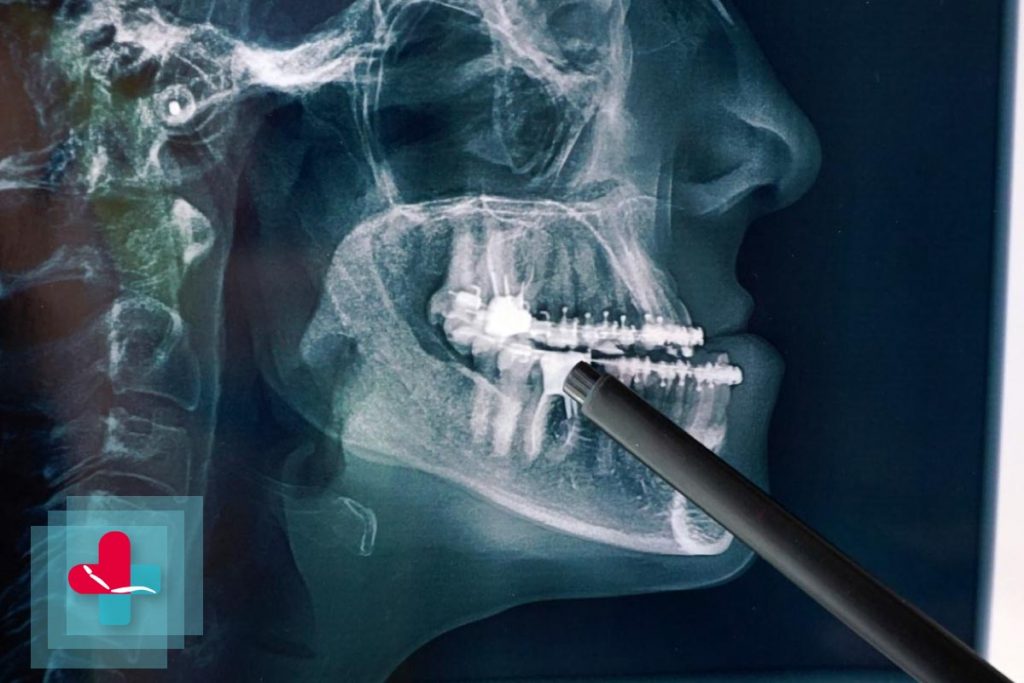

Non ha potuto aprire la bocca dalla nascita, per 16 anni ma adesso, grazie ad un intervento eccezionale di chirurgia maxillo facciale all’ospedale San Marco di Catania, Aurora (nome di fantasia) può cominciare una nuova vita fatta di parole, sorrisi, cibi solidi e tutto quello a cui ha dovuto rinunciare nel corso della sua vita. Si tratta del primo caso in Sicilia di questo genere, sono sei in tutta Italia, straordinariamente complicato, che ha richiesto mesi di studio preventivo affinché tutto andasse per il meglio, dicono dall’ospedale.

La forma della sindrome genetica di Nager di cui soffre Aurora dalla nascita è tra le più rare al mondo. In questo caso, già nel feto si era sviluppato un ammasso osseo che aveva fuso la mandibola al cranio non consentendo l’articolazione necessaria ad aprire la bocca. Il successo dell’operazione, durata circa dieci ore, è stato il frutto di un lavoro multidisciplinare, tra le varie équipe aziendali. Oltre ai chirurghi maxillo-facciali, in sala operatoria erano presenti in venti tra colleghi chirurghi anestesisti della Rianimazione sale chirurgiche e della Chirurgia toracica. “Tuttavia – dice l’ospedale – l’intervento non si sarebbe potuto realizzare senza la piena disponibilità del direttore generale dell’azienda ospedaliero universitaria etnea, Gaetano Sirna, che ha stanziato le risorse per la realizzazione della protesi in titanio impiantata nella giovane paziente, una vera e propria opera di bioingegneria tra le più moderne.